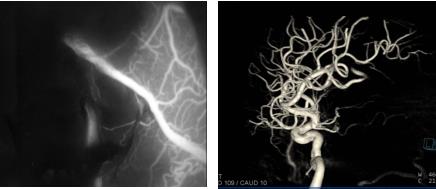

术后显微镜荧光造影及杂交手术室脑血管造影(DSA)显示血管畸形团全切

手术中,首先在神经导航下精准定位畸形血管团位置,然后根据术前多模态重建影像保护语言区脑组织,找到供血动脉,最后完整切除畸形血管团。双荧光手术显微镜荧光造影及MRI-DSA双杂交手术室术中脑血管造影(DSA)均显示血管畸形团已被全部切除。